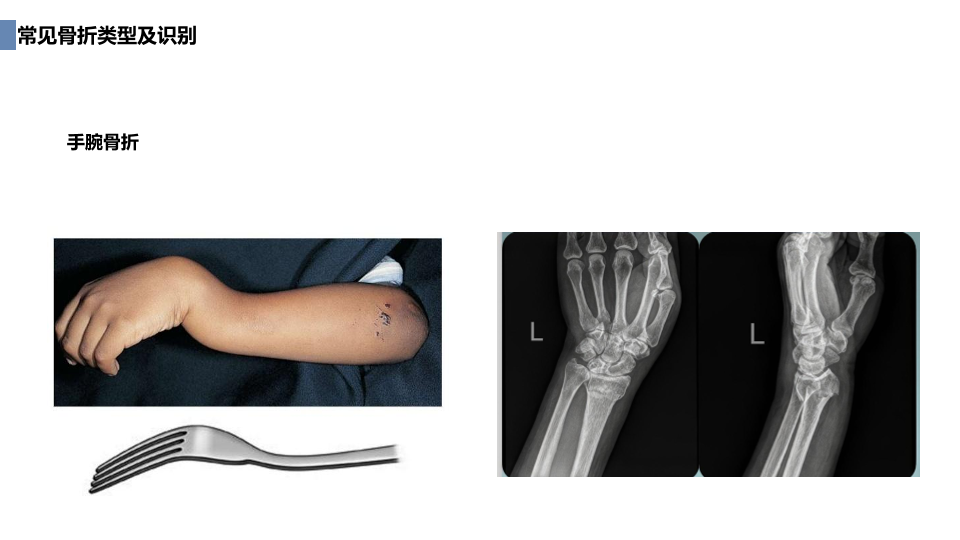

创伤骨科急救